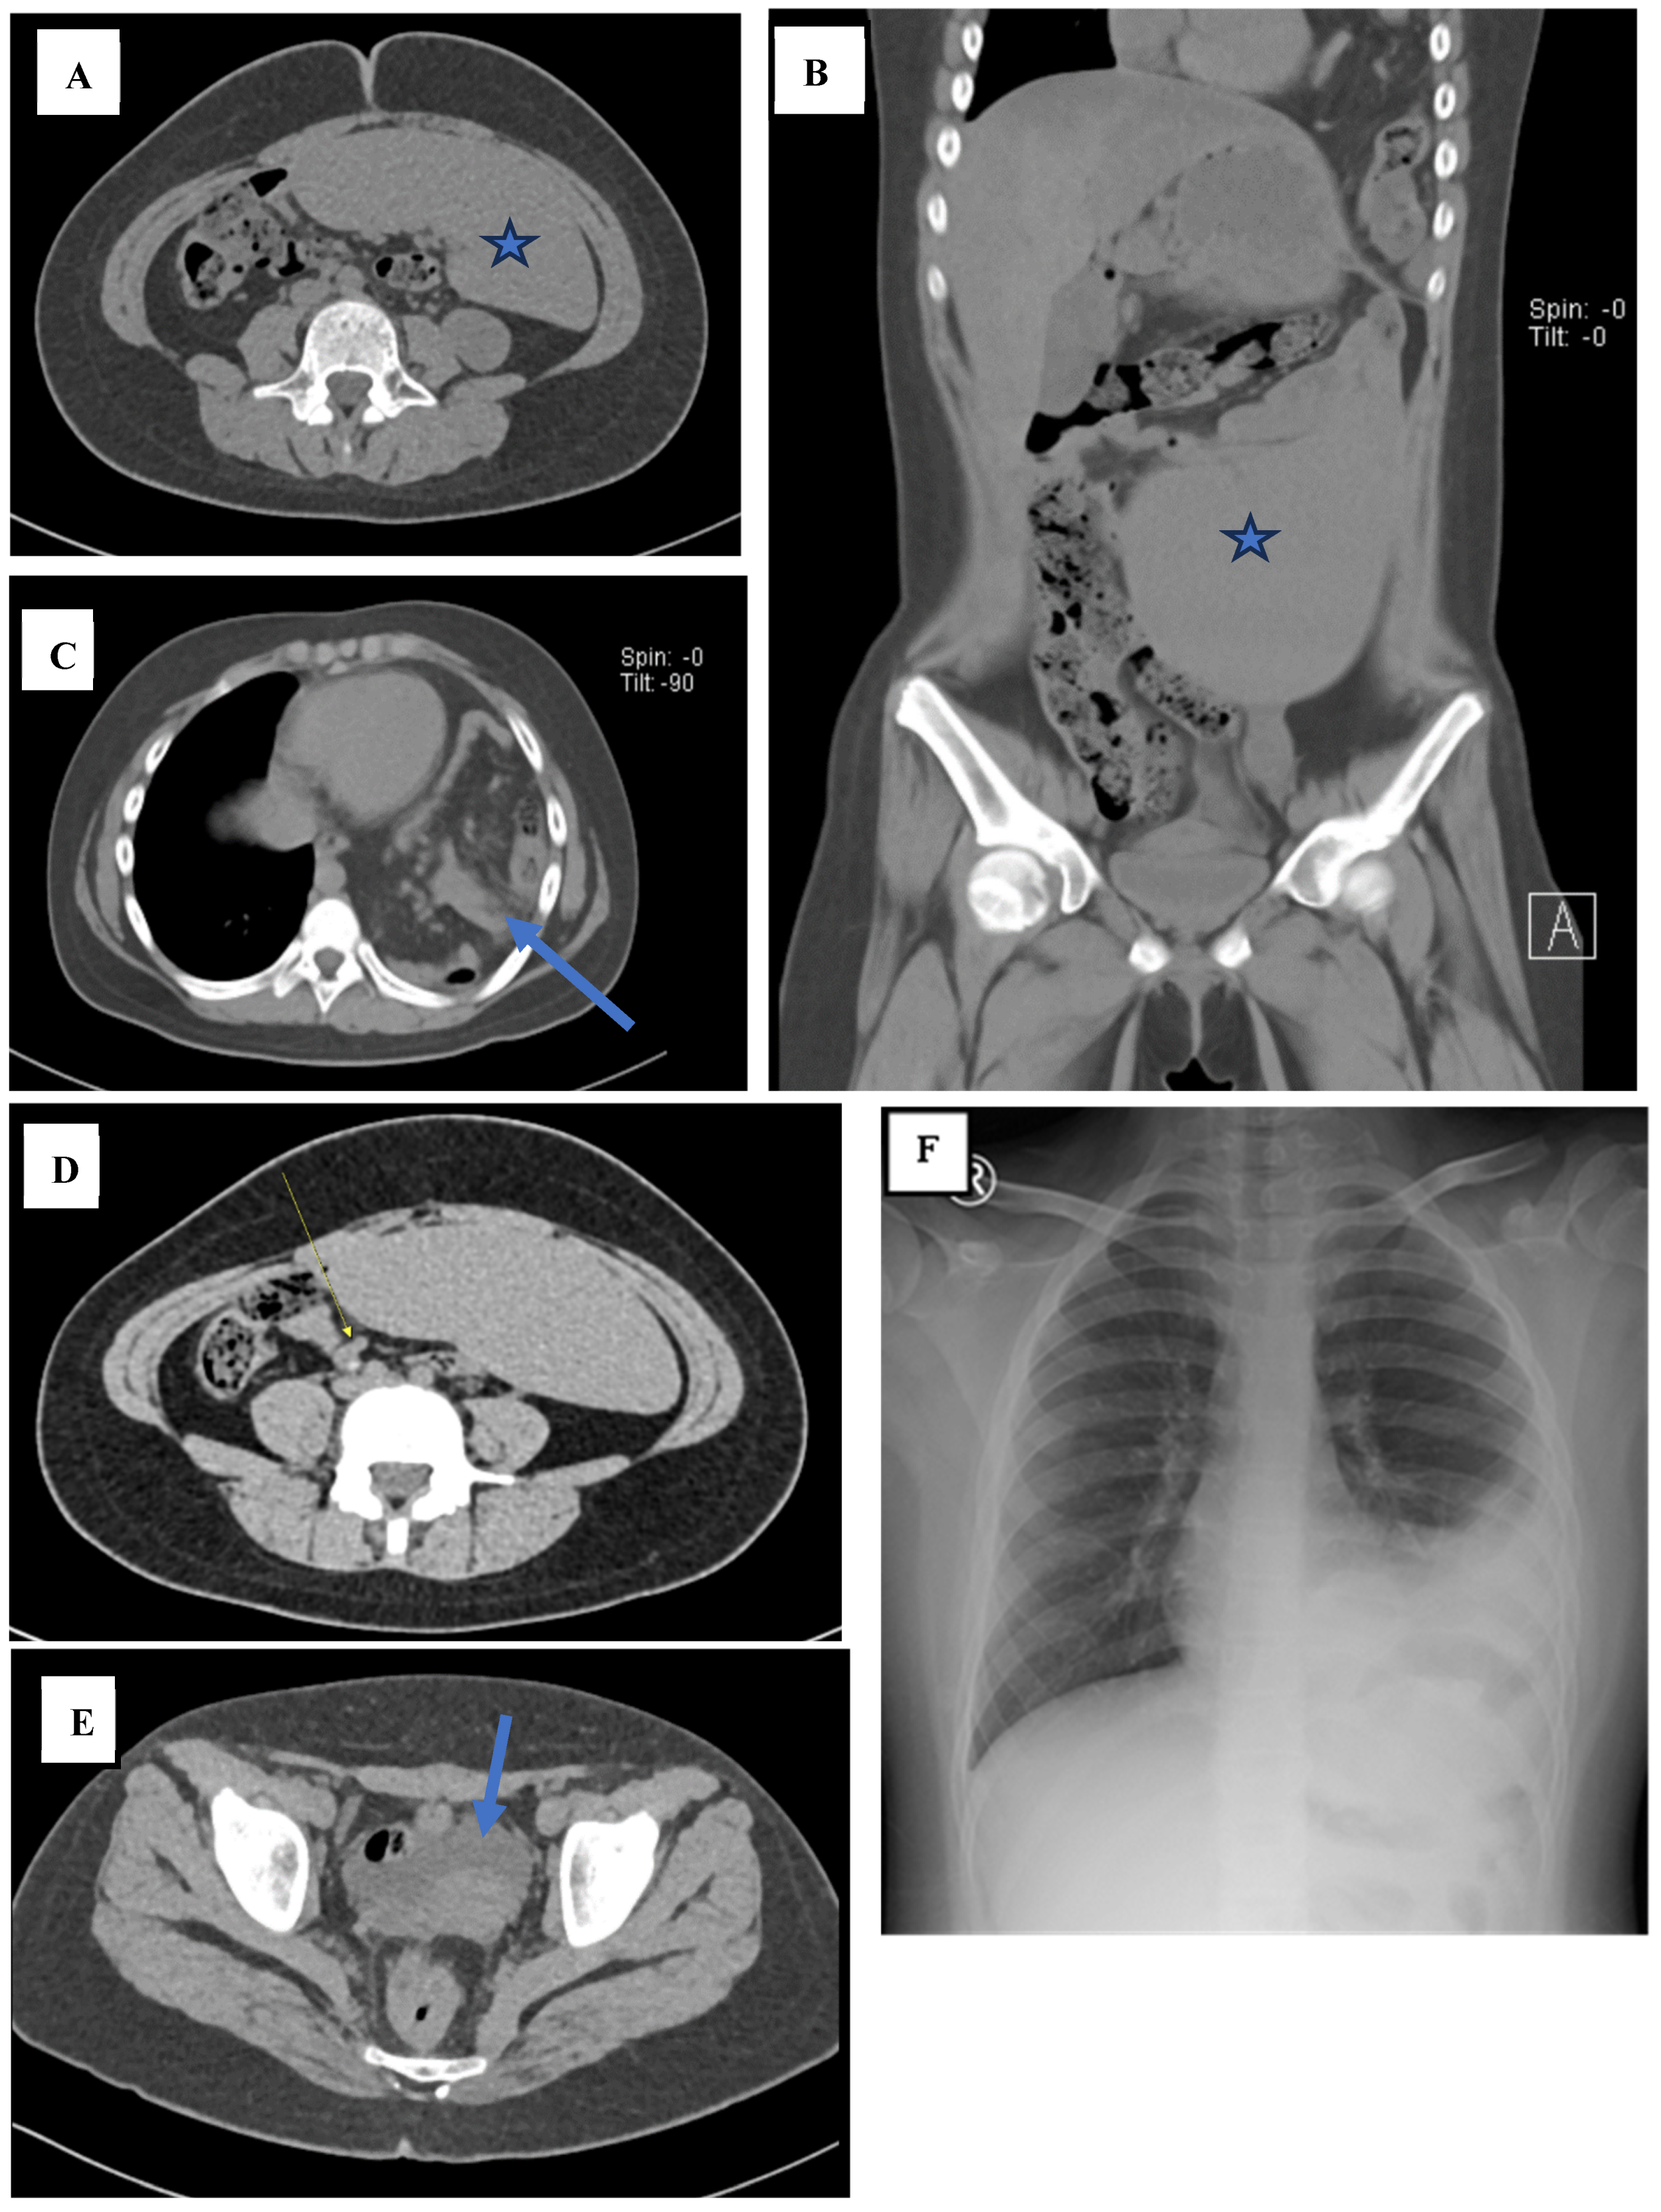

3. Case Presentation